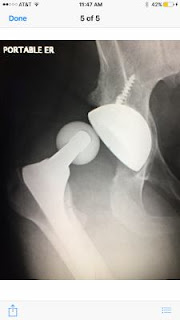

Last May my husband was putting on his shoes on the side of the bed when his hip replacement dislocated, and he fell to the floor in agony. Of course, he was alone in the house, and his cell was on the bureau on the other side of the room. Lucky for him, the house phone was on his nightstand, and he was able to call 911.